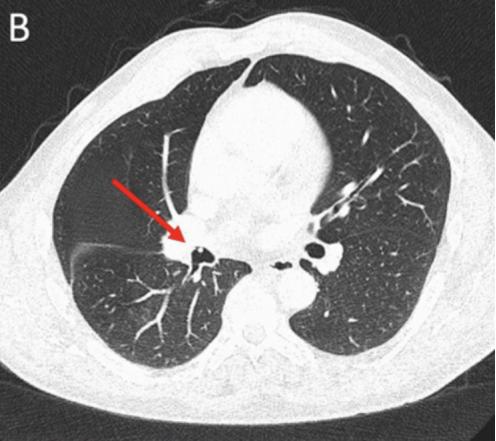

图2. 支气管镜影像CT检查怀疑恶性肿瘤

CT检查示右后上叶实变,没有看到含气支气管影,怀疑是支气管内肿瘤导致阻塞后实变(图1 A)。支气管内膜异常也出现在中间支气管和左主支气管(图1B、1C)。支气管镜检查显示,左侧主支气管、右侧中间支气管和右上叶后段支气管有大量息肉样肿块。(图2)